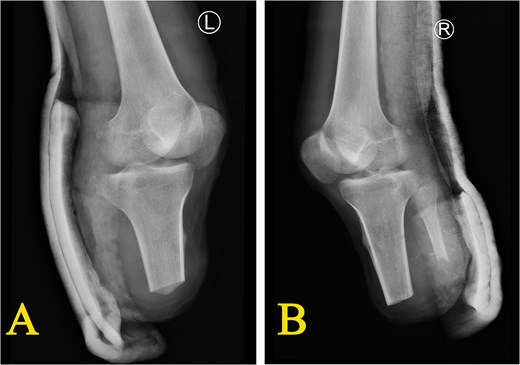

Upon admission, the emergency department witnessed that case’s right calf was completely severed, showing tendon retraction and exposure of the proximal tibia and fibula, with localized ischemic necrosis and moderate contamination of the wound (Fig. 1A). The left calf was also completely severed below the mid-shaft, leaving only 3 cm of skin, accompanied by significant distal tissue destruction characterized by comminuted fractures of the left tibia, calcaneus, and talus. The wound was moderately contaminated with extensive soft tissue damages (Fig. 1B).

Condition of both calves when arriving at the emergency room (D0) (A) the right calf: Completely severed with tendon retraction and exposure of the proximal tibia and fibula; moderate contamination of the wound; (B) the left calf: Completely severed below the mid-shaft, leaving only 3 cm of skin, accompanied by significant distal tissue destruction characterized by comminuted fractures of the left tibia, calcaneus, and talus.